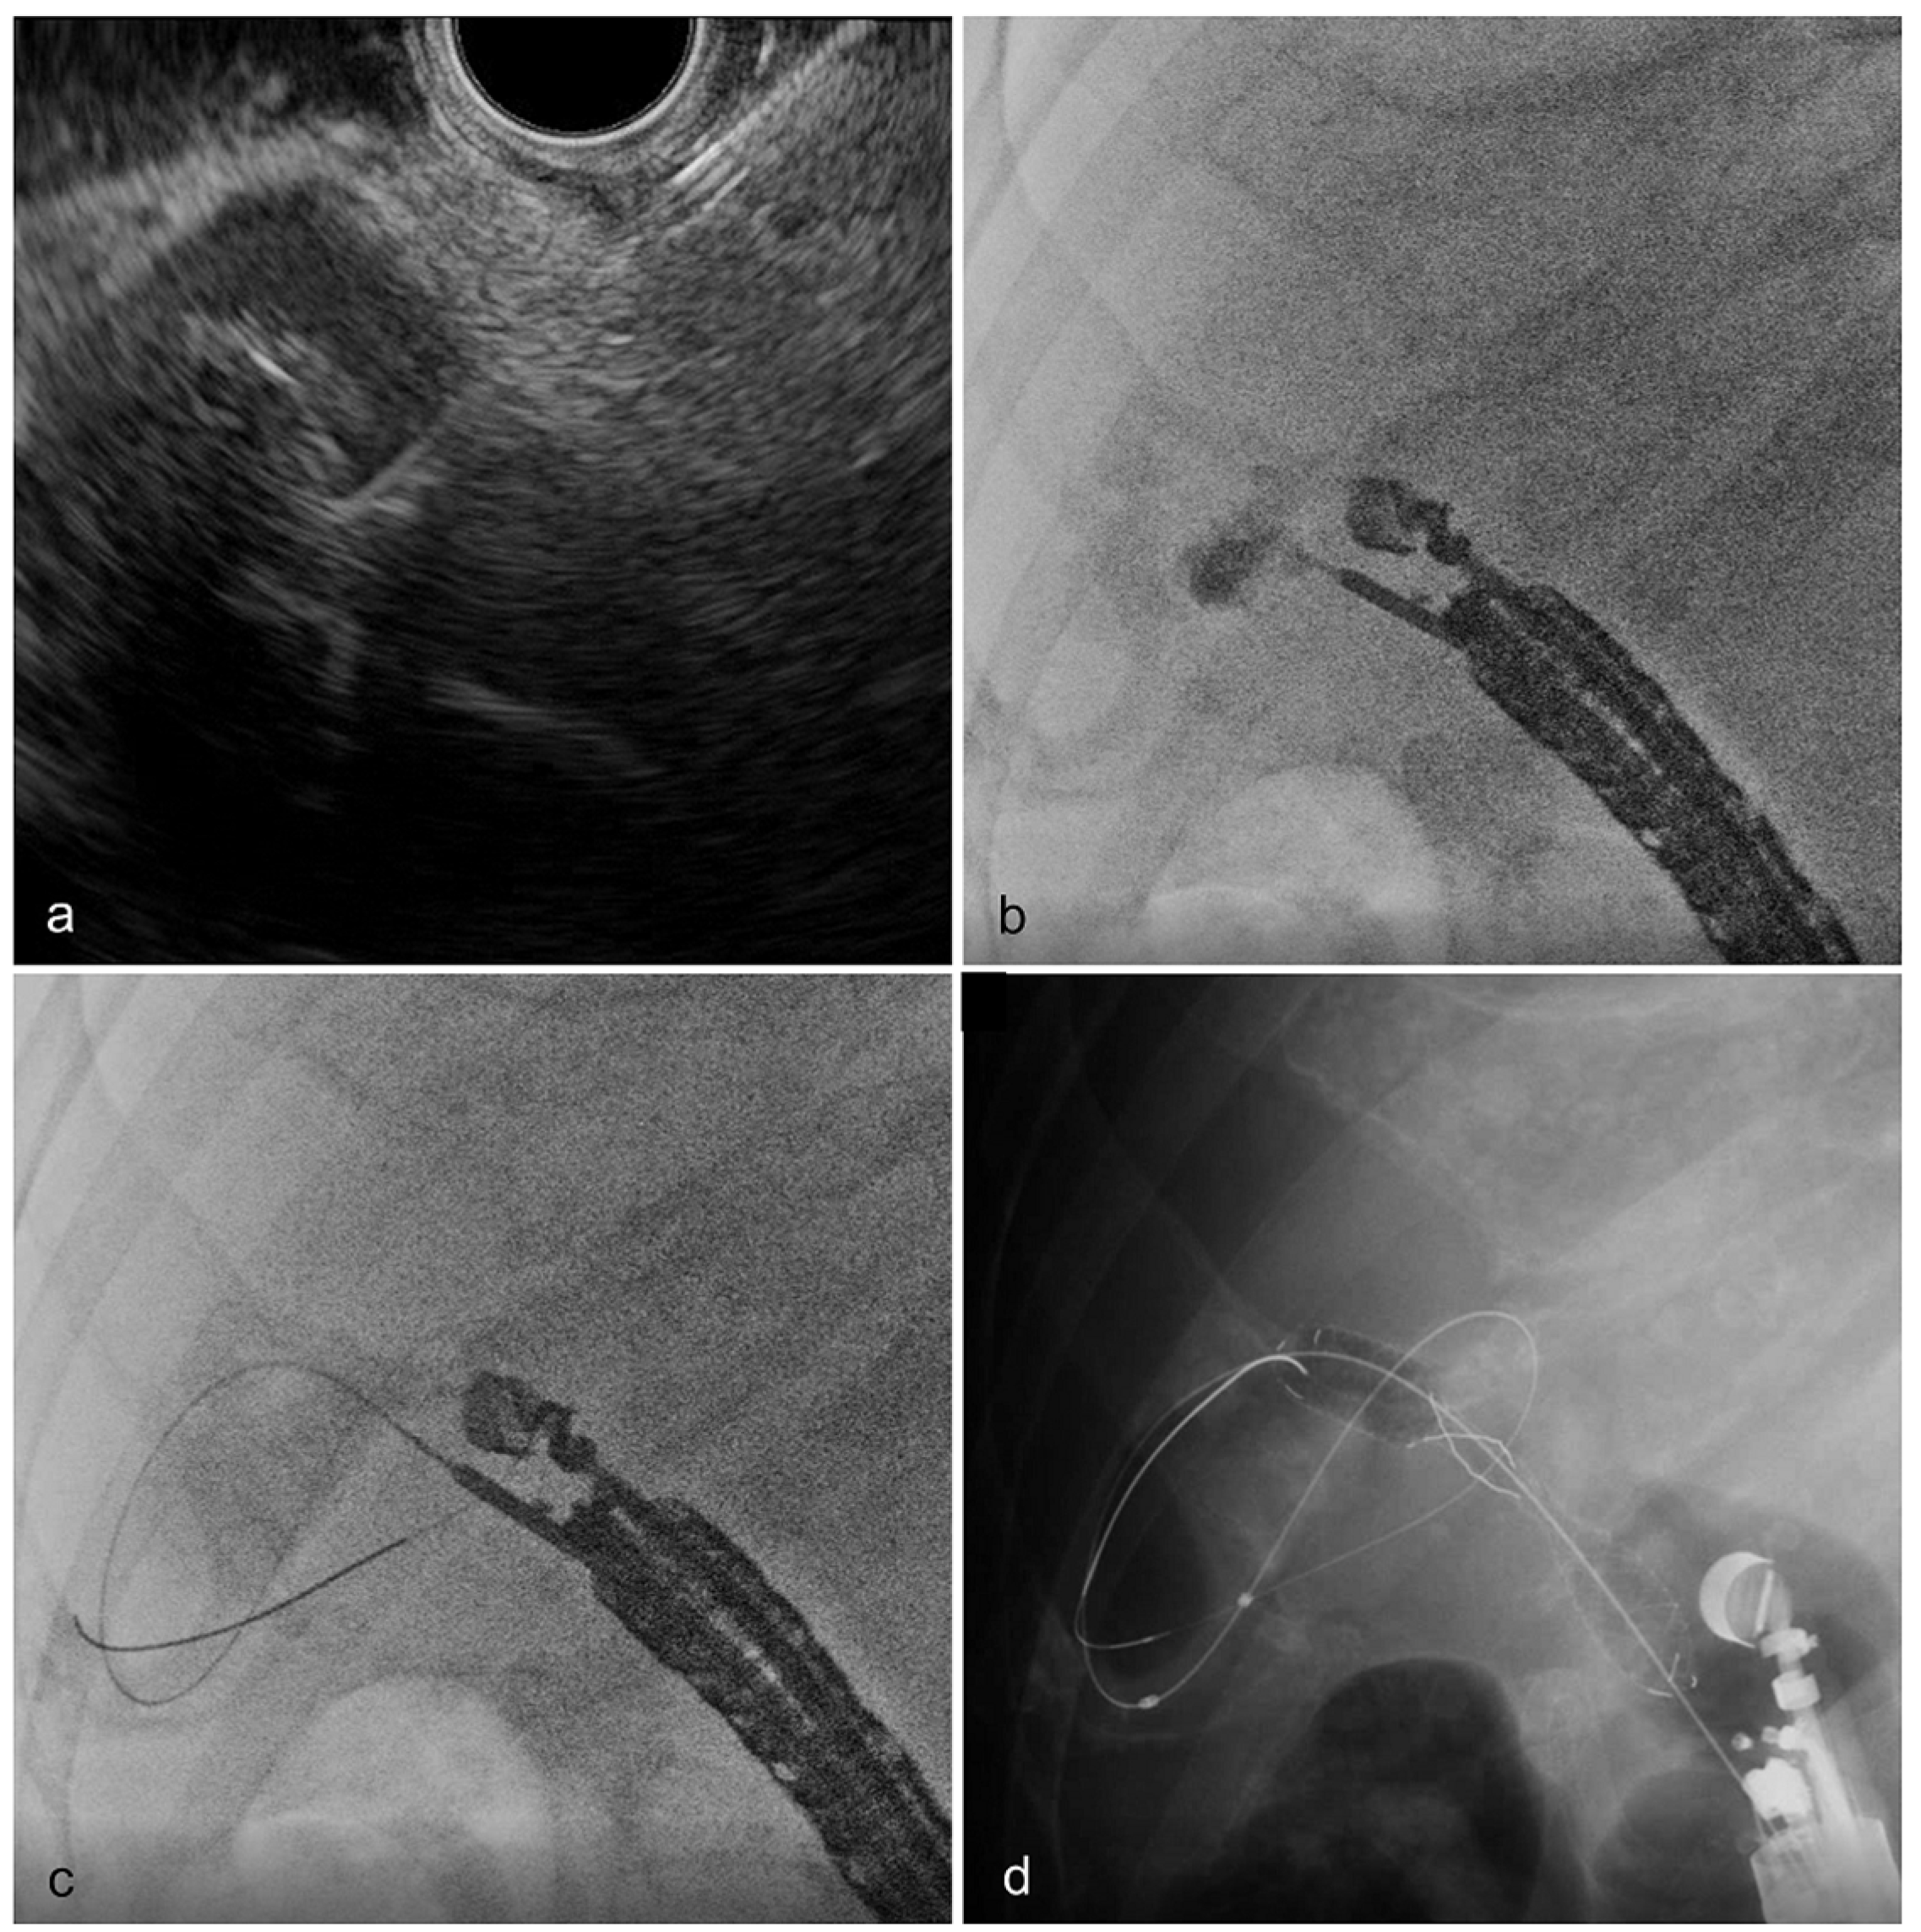

Endoscopic ultrasound showing a small gallbladder calculus Download Endoscopic Of Gallbladder Endoscopic gallbladder drainage can be considered in patients without evidence of gallbladder perforation or biliary peritonitis. Whether the approach to the management of gallbladder disease is surgical, endoscopic (as in the fairly recent introduction of natural orifice. Endoscopic ultrasound (eus) has a high spatial resolution that can improve the diagnosis of gb polypoid lesions, gb wall. Diseases of the gallbladder. Endoscopic Of Gallbladder.